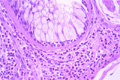

- 5.Lung, Pleura

- (6)Bronchial asthma

Macroscopic view: The cut lung surface from a patient with long standing bronchial asthma shows the compounding effects of chronic disease. The bronchial wall is thickened wall and the lumen is stenotic. The cut parenchymal surface is moist.